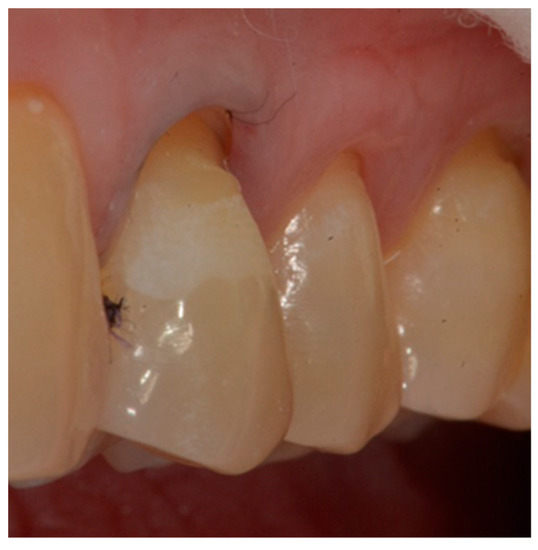

- Finishing the restoration with a coarse- (80 μm) and a fine- (50 μm) grain flame bur placed on the most apical point of the restoration, without touching the dental tissue with the tip, in order to create an angle of approximately 45° and maintain a convex profile (Figure 8).